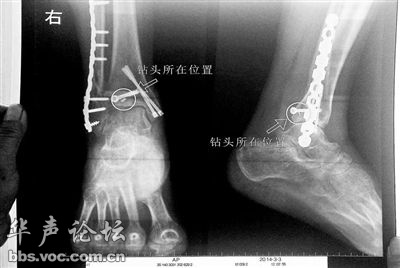

胡女士于2013年3月在北京市丰台区右安门医院进行了一次骨折手术,术后医生才发现手术时用来打眼用的钻头找不到了,后拍X片才发现钻头被医生不慎遗留在了胡女士的骨头中,并且无法取出。她与右安门医院进行交涉,索赔12万元。而右安门医院未与胡女士达成一致,称钻头在体内并不会产生多大的危害。(北京青年报3月24日)

首先我们来看医院声称的所谓双方共同承担的医疗风险,大家知道,手术确实是存在诸多医疗风险的,这包括比如手术中患者对麻醉的不良反应、比如患者受到感染、突然的心脏衰竭等一些风险,这些都属于不可控的风险,包括医生在手术过程中无明显过错;医院一般为了规避风险责任,都会在手术前详细罗列他们专业上所有能想象到的风险,然后让患者家属签字,但不论医院如何发挥想象力,他们也不会在术前的双方协议中写上手术工具遗留在患者体内之类的风险。毫无疑问的是医生将手术工具遗留在患者体内,完全是院方单方面过错造成的,而且这是完全可控的。退一步说这根钻头并非手术时折断在患者骨头里无法取出来等特殊情况,而完全是术后医生马虎大意,术后才发现找不到钻头了,患者回忆,开刀医生说在手术室地面上找了好久也没找到,当时就怀疑也许遗留在她的骨头里了,只是之后照X片被证实。

其次就是所谓的“不锈钢钻头留存体内无害”论,对患者和家属来说这就已更不是什么推脱责任的理由了,医生总能从自己的专业来忽悠并不专业的患者,比如医院方面声称“留在她腿里的钻头确实无法取出,按常理说,钻头不应该断在里面,但现在事情确实发生了。钻头没有折在关节,而是在跖骨内,跖骨主要起支撑作用,不像关节那样起活动作用,而且这个部位比较质密,并非像肌肉要经常活动受到挤压--------”。确实,从专业的角度说,绝大多数人并不懂医术,当然也不懂不锈钢钻头留在身体内到底有没有害处,这需要专业的判断。但医院这样说,明显是在为自己的工作过错寻找专业的理由,不锈钢钻头在体内有没有害处其实也不应该是当事医院自己来说,需要医疗鉴定,何况医院方面也只是说“按照照片里的位置,相对来说是没有害的”,一句“相对而言”,本身就已经透露出并不靠谱的结论。就算真的没有害处或害处不大,但作为患者,至少心理上会留下沉重的阴影,谁会希望在自己体内留下一个医学上并不需要的完全多余金属异物呢?